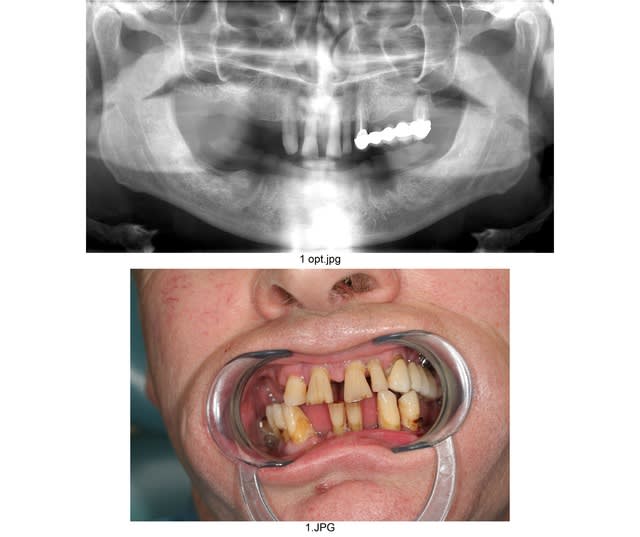

Pour ce cas, au maxillaire, la patiente a accepte un devis de 3500€ pour un complet sur barre avec 4 implants.

sur la deuxieme photo, j'ai notifie des longueurs approximatives pour les epaisseurs d'os disponibles.

Que pensez vous d'un all on 6 avec les 6 anterieurs ?

Ps: la patiente n'a pas forcement les moyens de faire un bridge sur 8 implants...

patiente motivée et sympa, sourire pas du tout gingival, de l'os assez bien exploitable (un peu moins du cote de 25-26, mais je vais me débrouiller soit avec implants courts 6 ou 8mm, soit avec une Summers et poser des 10mm)

Niveau nombre d'implants , je vais plutôt tabler soit sur 8 ou 9 implants et remplacer de 16 à 26.